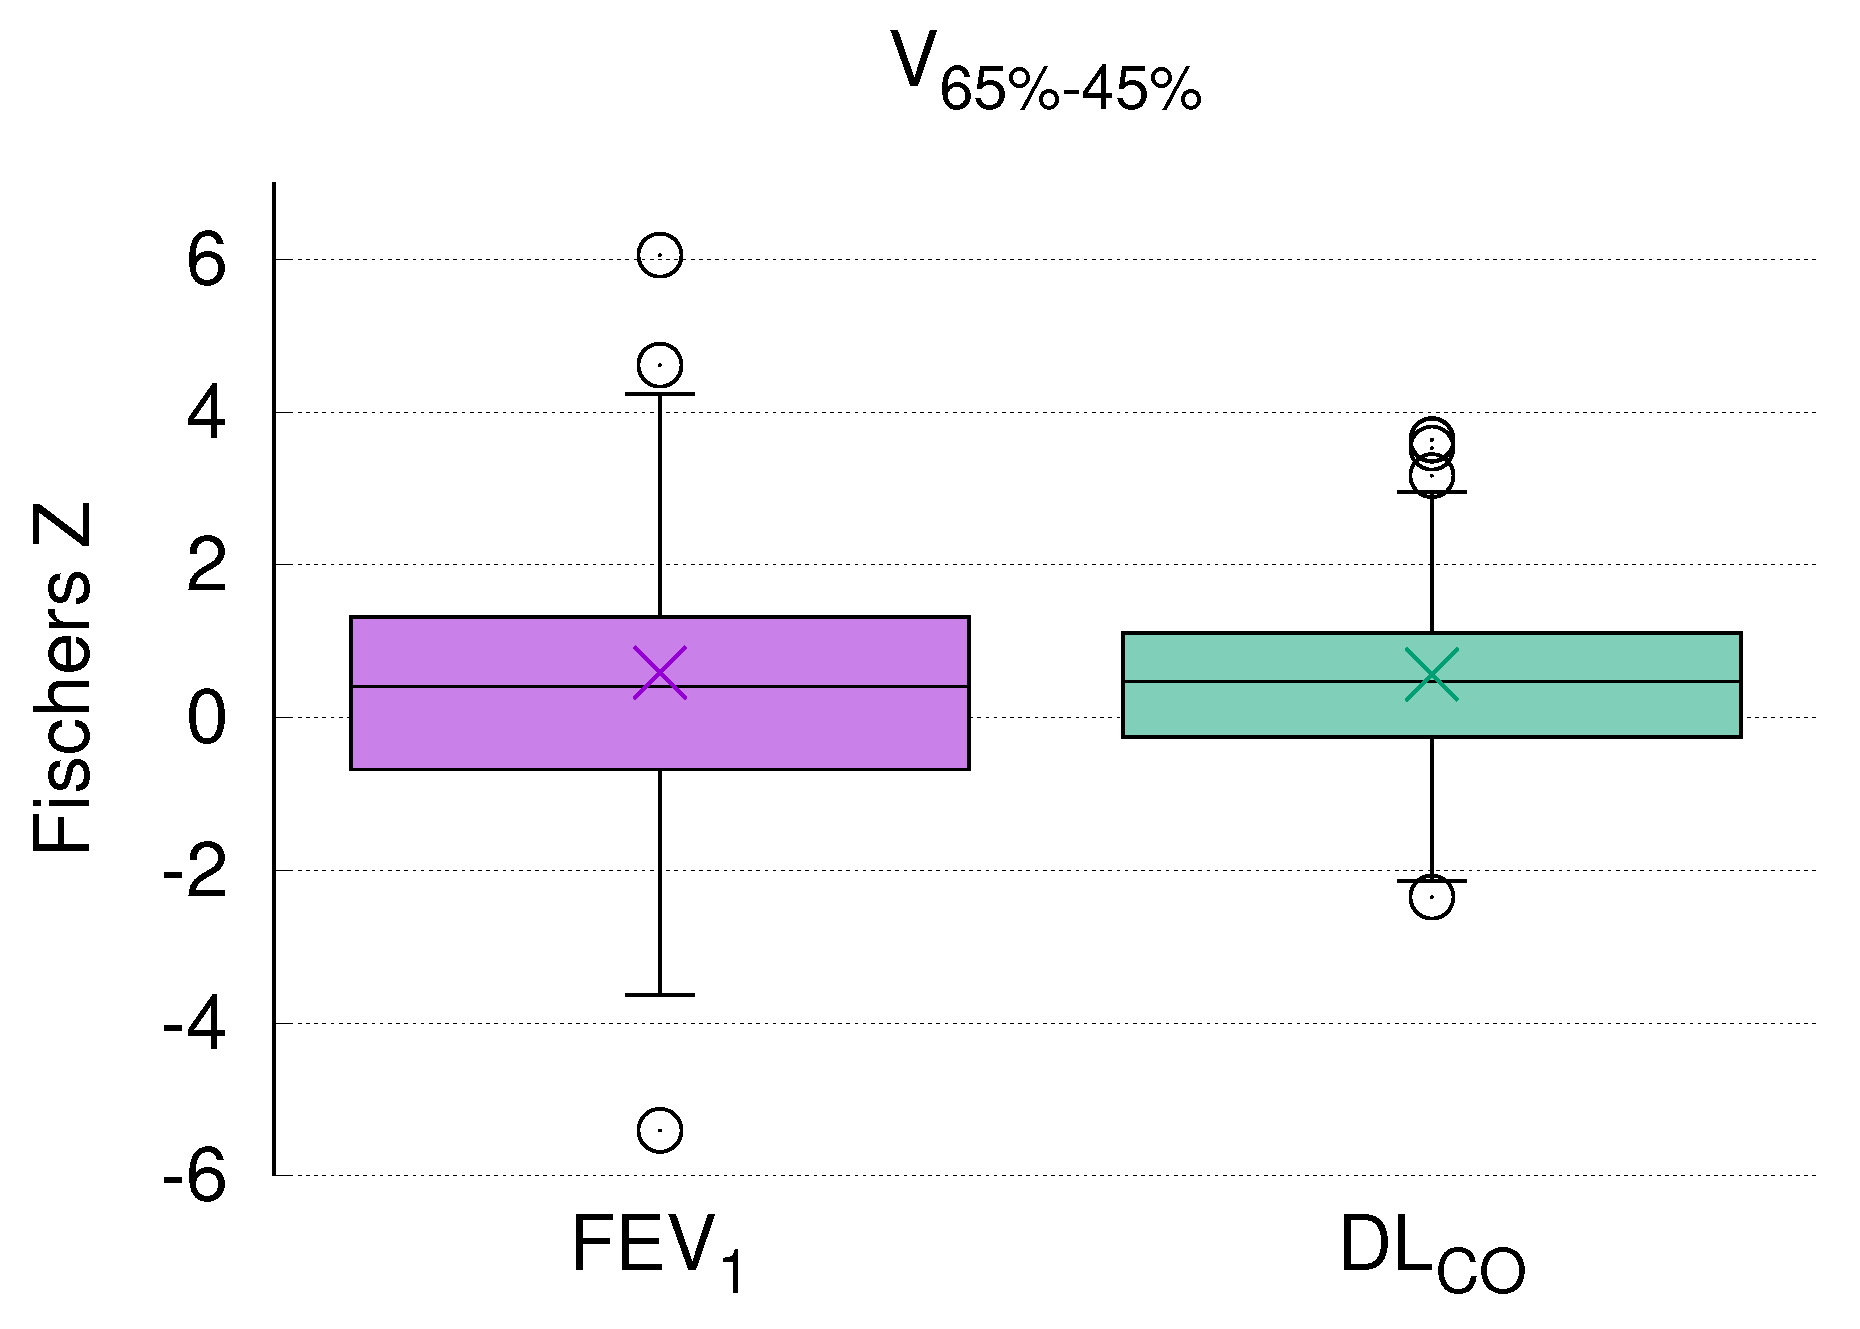

3.5. DL Correlates with V

3.6. PFT and CT Density Changes after RT